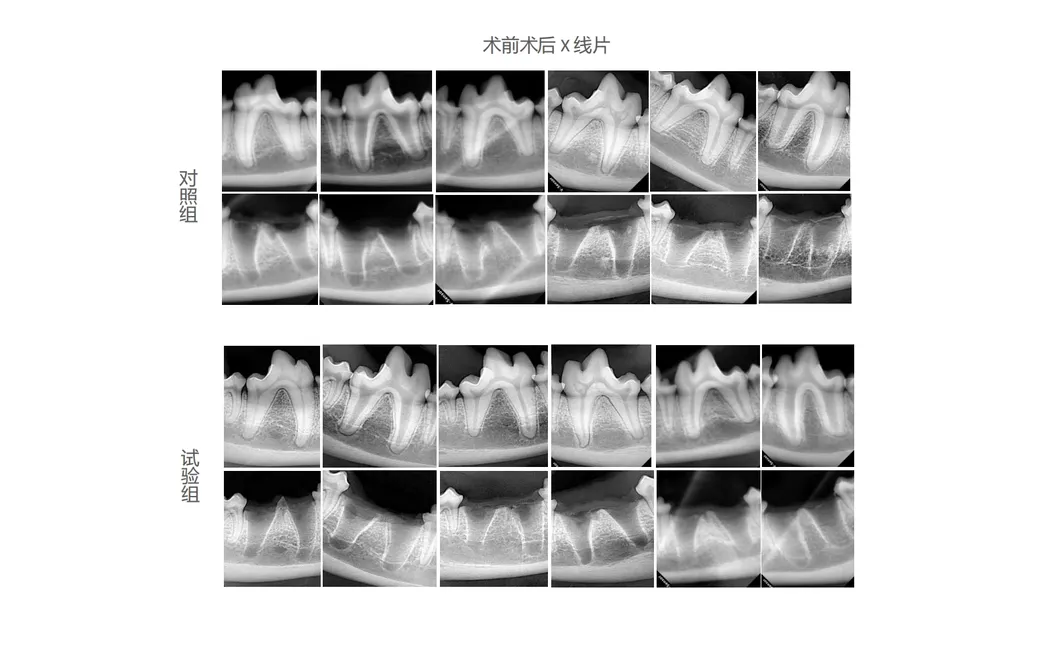

This study evaluated the effectiveness of state-of-the-art dental tools for veterinary use. The treatment group utilized the revolutionary Pneumatic Dental Elevator Kit. Critical factors observed included physiological parameters, intraoperative complications, extraction duration, and socket damage. Rigorous statistical analysis highlights the superior performance of these advanced tools.